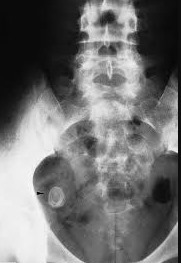

Q

Que espera encontrar en estudios de imagen RX en apendicitis?

A

Rx: asa de centinela, borramiento del musculo psoas; niveles hidroaéreos.